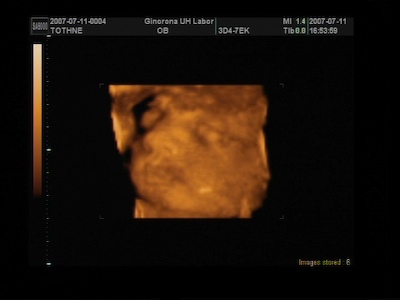

A 4D-s vizsgálaton nekem azt mondták ,hogy 5 nappal kisebb a baba, de ez még belefér ezért nem változtattak semmin , és lehet,hogy még előbb is kibújhat.